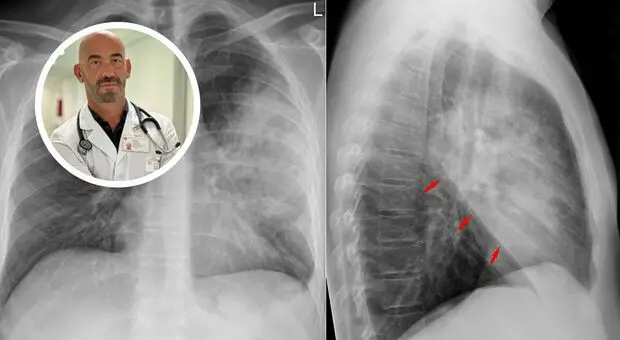

Polmonite, boom di casi. Bassetti: «Ospedali già pieni». Sintomi, cause, cure e cosa non fare

«I nostri ospedali sono già oggi pieni di casi di polmonite», avverte Matteo Bassetti, direttore Malattie infettive dell'ospedale policlinico San Martino di Genova. Ogni...